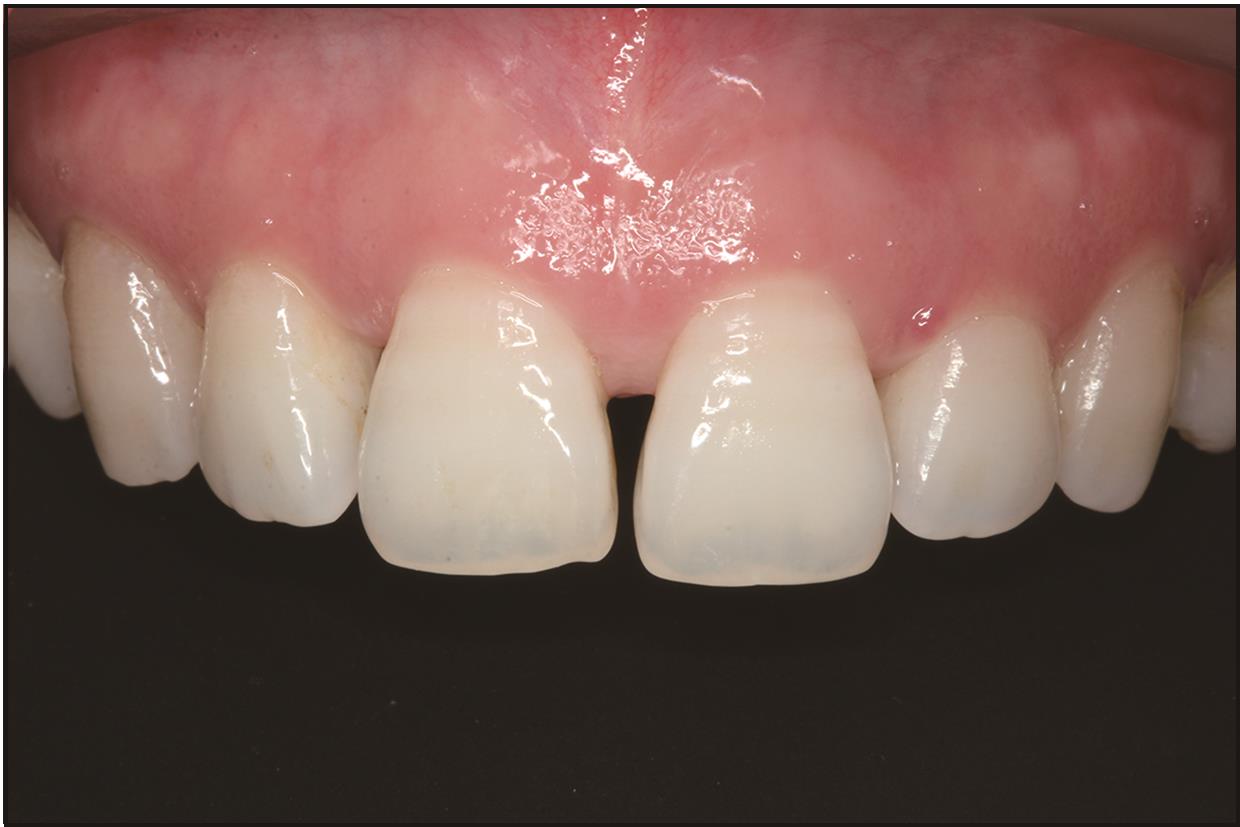

图 5

术中去除成型片即刻的效果A:正面像;B:腭面像;C:牙科显微镜下唇、腭面像。"